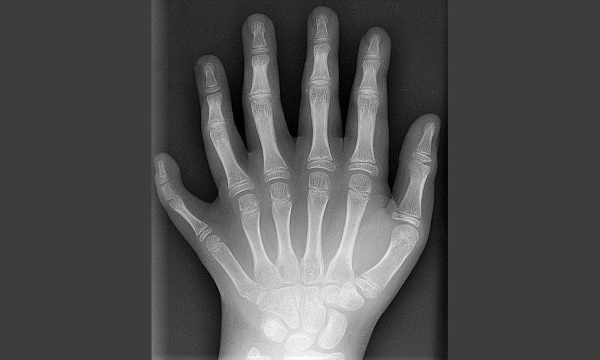

Radiographie de la main d’un patient polydactyle. Radiographie en projection postérieure-antérieure de la main gauche d'un enfant de 10 ans...